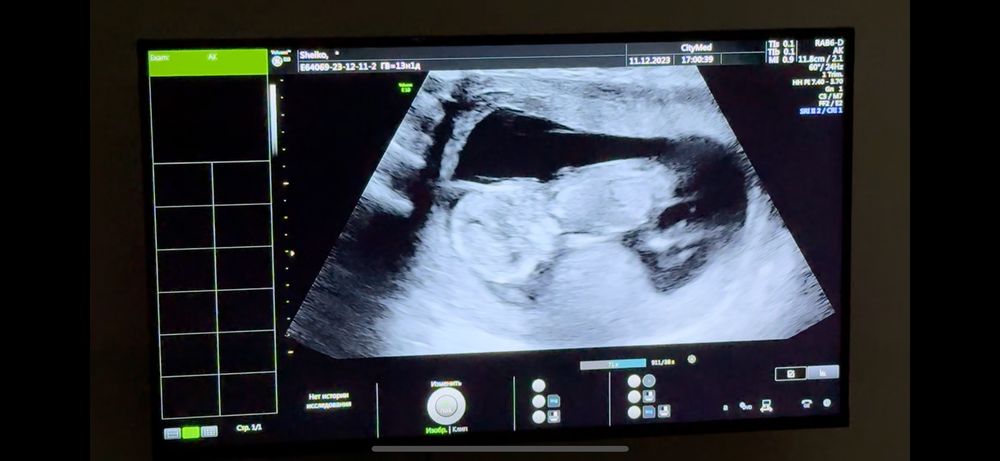

Мальчик или девочка?)

Срок 13+2 по ктр 😁😁😁 Я все узи снимала на видео, вот скриншоты)))

Узист предположил девочку) так ли это?)🥹🥹🥹

Мне кажется он спиной лежит😐 и у вас тонус)